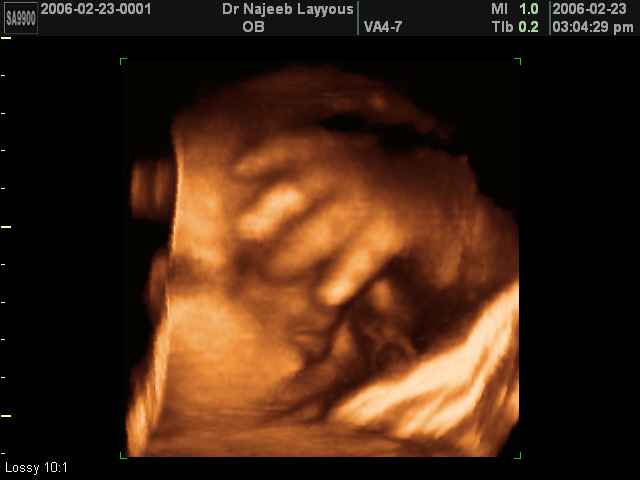

3D Ultrasound Scan Photos of Fetal Limbs | Dr N Layyous

3D Fetal Limbs Ultrasound Scan Photos